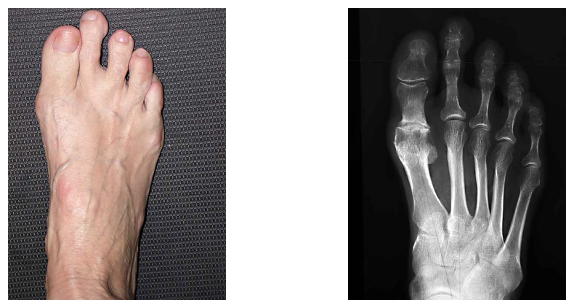

Deutlich ausgeprägte Arthrose und kurzer erster Mittelfussknochen

HemiCap / Toe Motion / Grosszehengrundgelenkprothese

Da der erste Mittelfussknochen nicht beliebig verkürzt werden darf, kann nun mit dieser neuen Methode der zerstörte Knorpel des Gelenkköpfchens durch eine anatomisch richtige Halbprothese, bestehend aus einer Verankerungsschraube aus Titan mit aufgesetzter Stahl- "Kappe", ersetzt werden. Bisherige Erfahrungen zeigen eine Verbesserung der Gelenksfunktion um mindestens 60% mit einem Rückgang der Schmerzen meist bis zu deren vollständigem Verschwinden.

Vor dem Eingriff: praktisch steifes Grundgelenk und starke Schmerzen

Befund nach 3 Monaten: eindrücklich die fehlende Schwellung und die gute Funktion